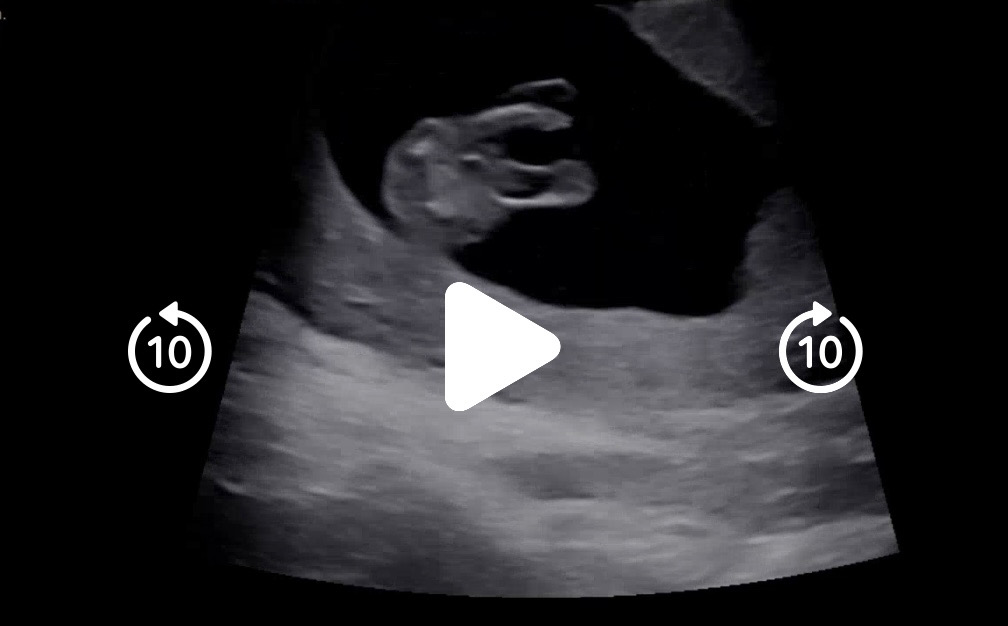

12주4일차 성별 …

다리사이같은데 정말 아들일까요..?

12주엔 여아든 남아든 다 튀어나와(?)있지 않나요ㅎㅎㅎㅎ각도법으로 보면 그래도 정확한 것 같아요

각도법으로보면 아들인게 정확하다는건가요??